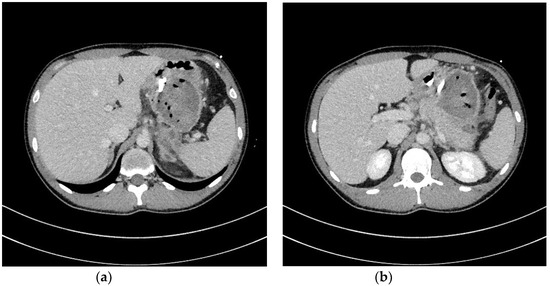

- Jagielski, M.; Smoczyński, M.; Studniarek, M.; Adrych, K. Endoscopic drainage combined with percutaneous drainage in treatment of walled-off pancreatic necrosis- a single center experience. Prz. Gastroenterol. 2018, 13, 137–142. [Google Scholar] [CrossRef] [PubMed]

| Percutaneous drainage | Drainage enables to insert a drain transperitoneally or retroperitoneally into the lumen of necrotic cavity under control of ultrasonography or computed tomography and to flush the necrosis with saline solution through the percutaneous drain. This technique may be used as the only way to approach the necrosis or as additional approach (according to ‘step-up approach’ strategy). |